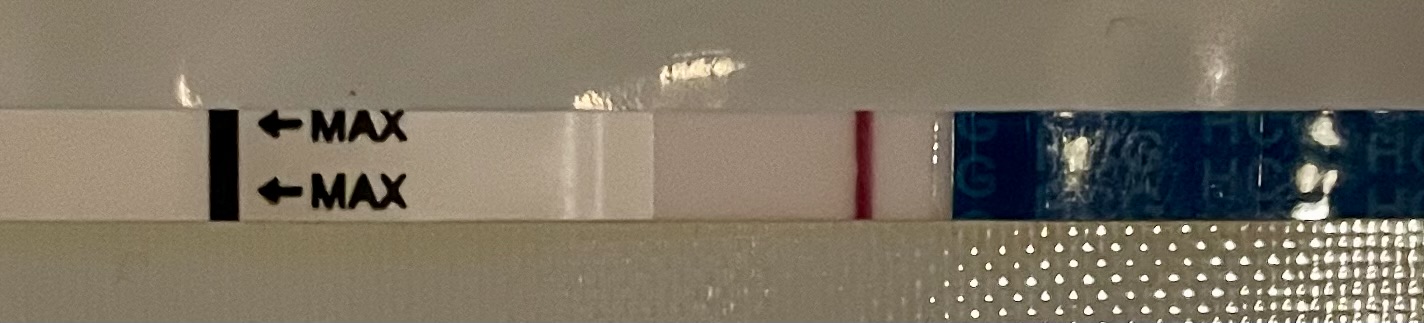

Jos mulla olikin ovis vasta tuossa kp25 niin mennään ihan samassa dpo:ssa! Testailen jo lauantaina, kun ei varmuutta oviksesta. Testaa ihmeessä sunnuntaina, jos jotain jo näkyisi

tänään siis dpo9 tai dpo7.